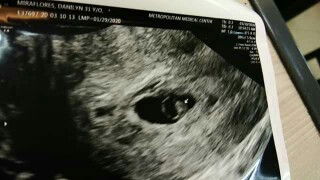

Hi sa mga octoberian due. Kmusta na?? Konting kembot nalang.???. October29 po ako.. Kayo???

Oct 29 dn ako.. 😍

Oct 29 daw tpos minsan nov 3